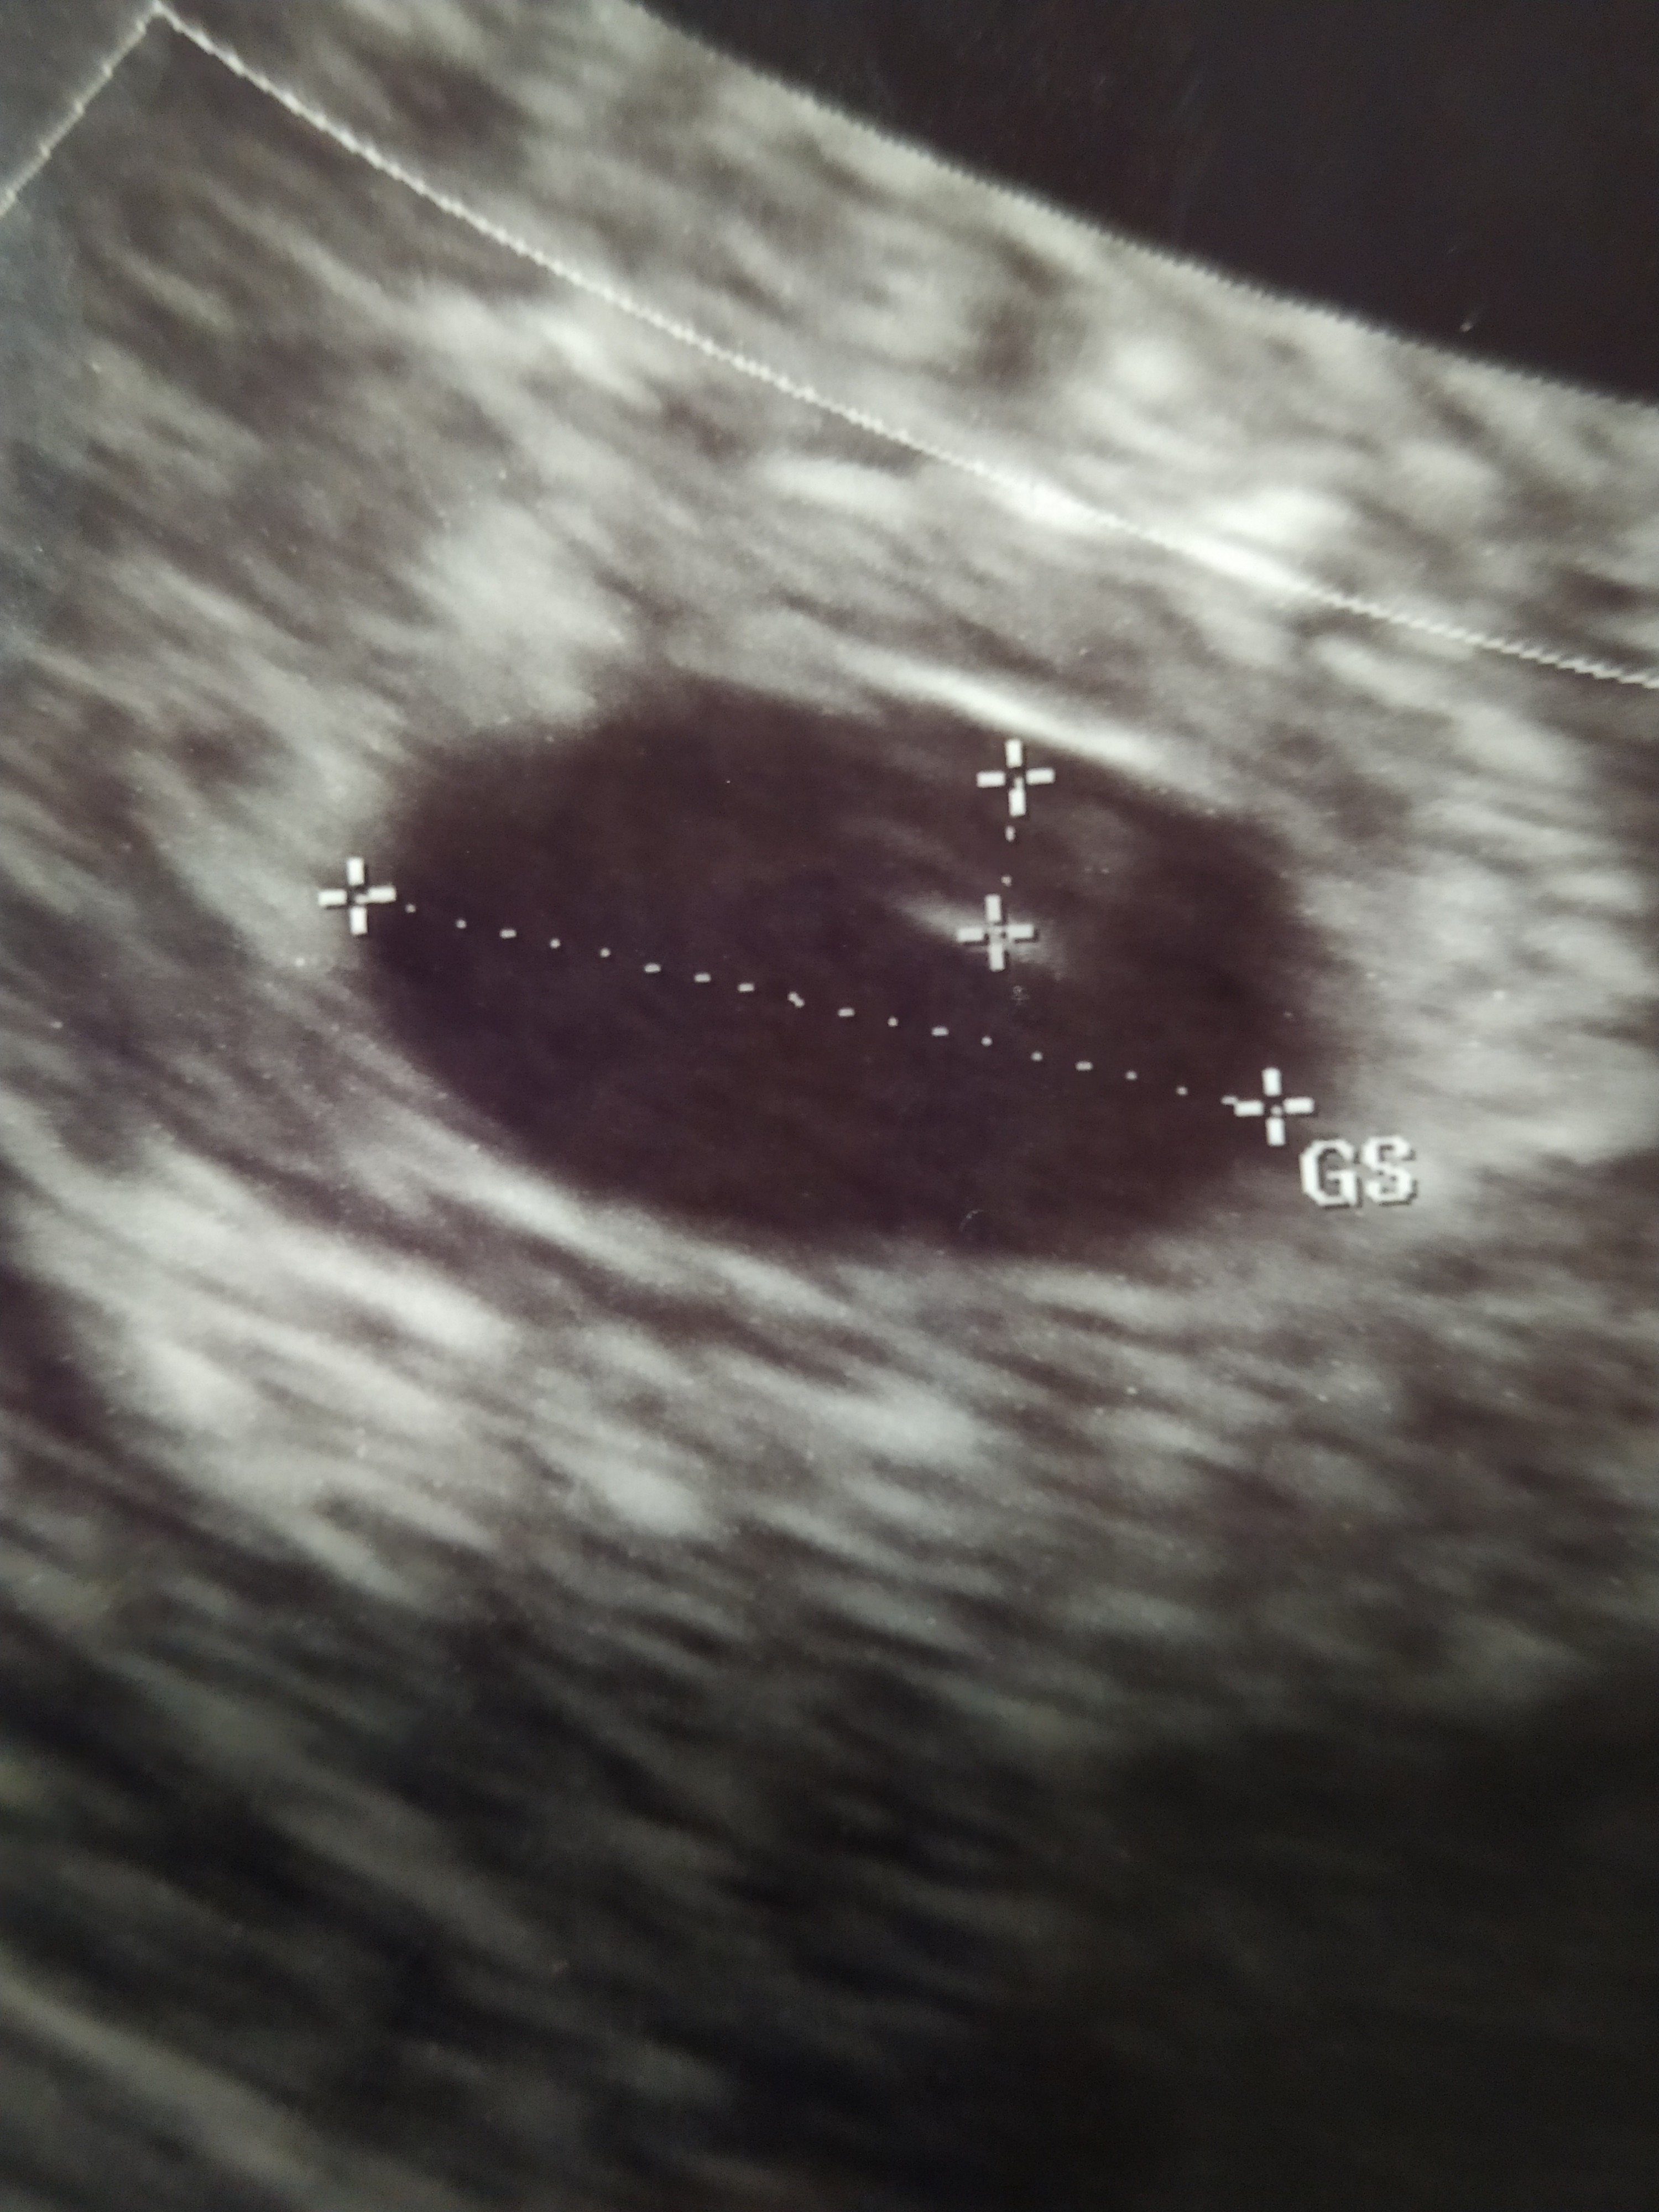

To ja już jestem po wizycie. Jest pęcherzyk ciążowy na miejscu + widać pęcherzyk żółtkowy, ale ciężko na razie z uwidocznieniem czegoś więcej. A liczyłam już na serduszko 😒

Ginekolog miał problem, musiał trochę uciskać mi brzuch, ponoć ułożenie macicy niekorzystne dla dobrego obrazu.

No i nadal człowiek czeka w zawieszeniu..

Tak, dodaję ;) aplikacja jeśli liczyć od om to powinno być 5+3. Ale jestem pewna, że owulacja była wcześniej niż powinna być, dlatego według mnie to już jest jakieś 5+5 lub nawet 5+6. Dlatego liczyłam na coś więcej.

Super ❤️ u mnie według om znowu 6t3d, ale znowu ja jestem pewna, że owulacja mi się opóźniła o jakieś 5 dni i wychodzi 5t5d. Tak jakbyśmy się zrównały. 😊 Oby już na następnym usg było u nas coś widać. Jest pęcherzyk żółtkowy to lada chwila pojawi się maleństwo ❤️ A masz wymiar pęcherzyka? U mnie na usg nie ma właśnie, w niedzielę na ip (trzy dni przed wizytą u mojej lekarki) miał 8 mm. A chyba mi urósł 🤔